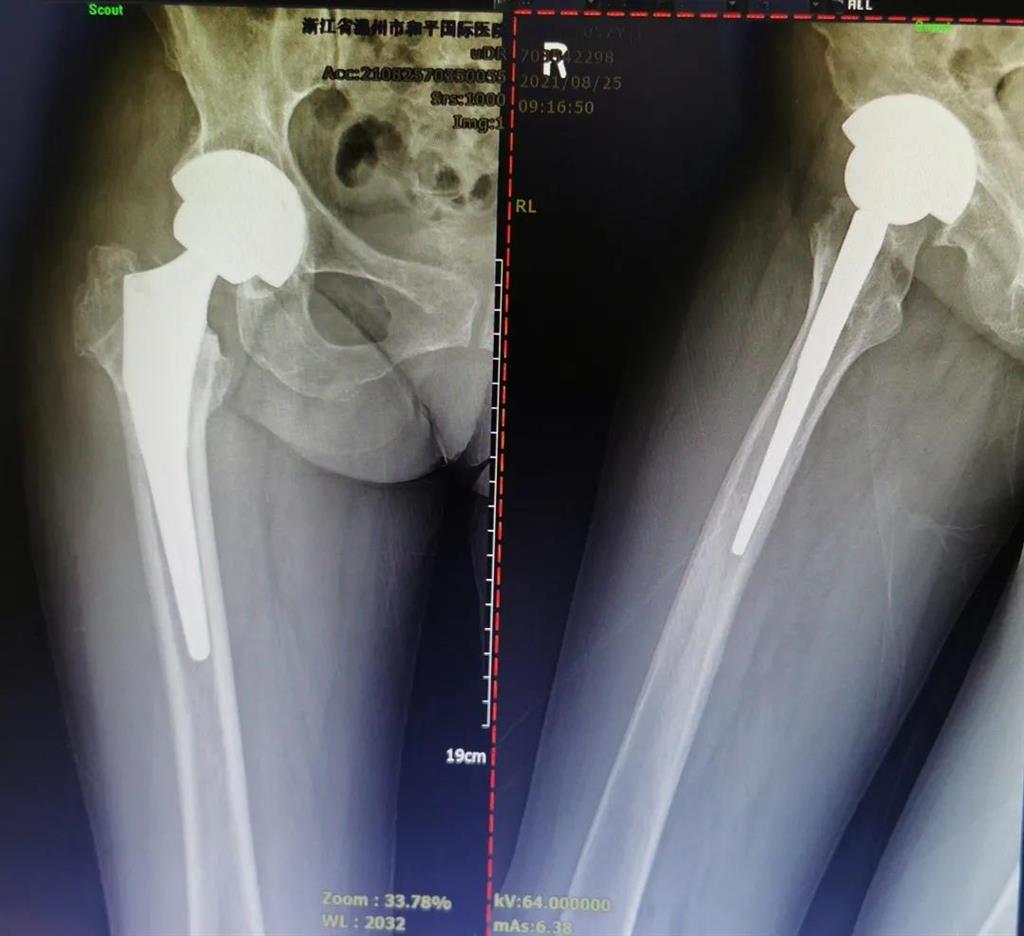

(△術(shù)前影像,右股骨頸骨折內(nèi)固定術(shù)后股骨頭壞死)

(△做完“右股骨頸全髖關(guān)節(jié)置換術(shù)”后的影像)